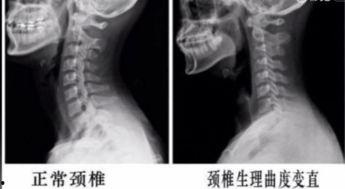

你是不是也和我一样,长时间对着电脑工作,感觉脖子酸酸的,颈椎不舒服呢?别担心,今天我就要给你带来一份特别的礼物——颈椎运动视频教程!跟着我,一起动起来,让你的颈椎重获新生!一、认识颈椎的重要性你知道吗,颈椎可是人体非常重要的部位哦!它不仅支撑着我们的头部,还负责传递大脑和身体之间的信息。但是,由于现代生活方式的改变,很多人都在不知不觉中伤害了它。所以,了解颈椎的重要性,是我们开始运动的第一步。二、